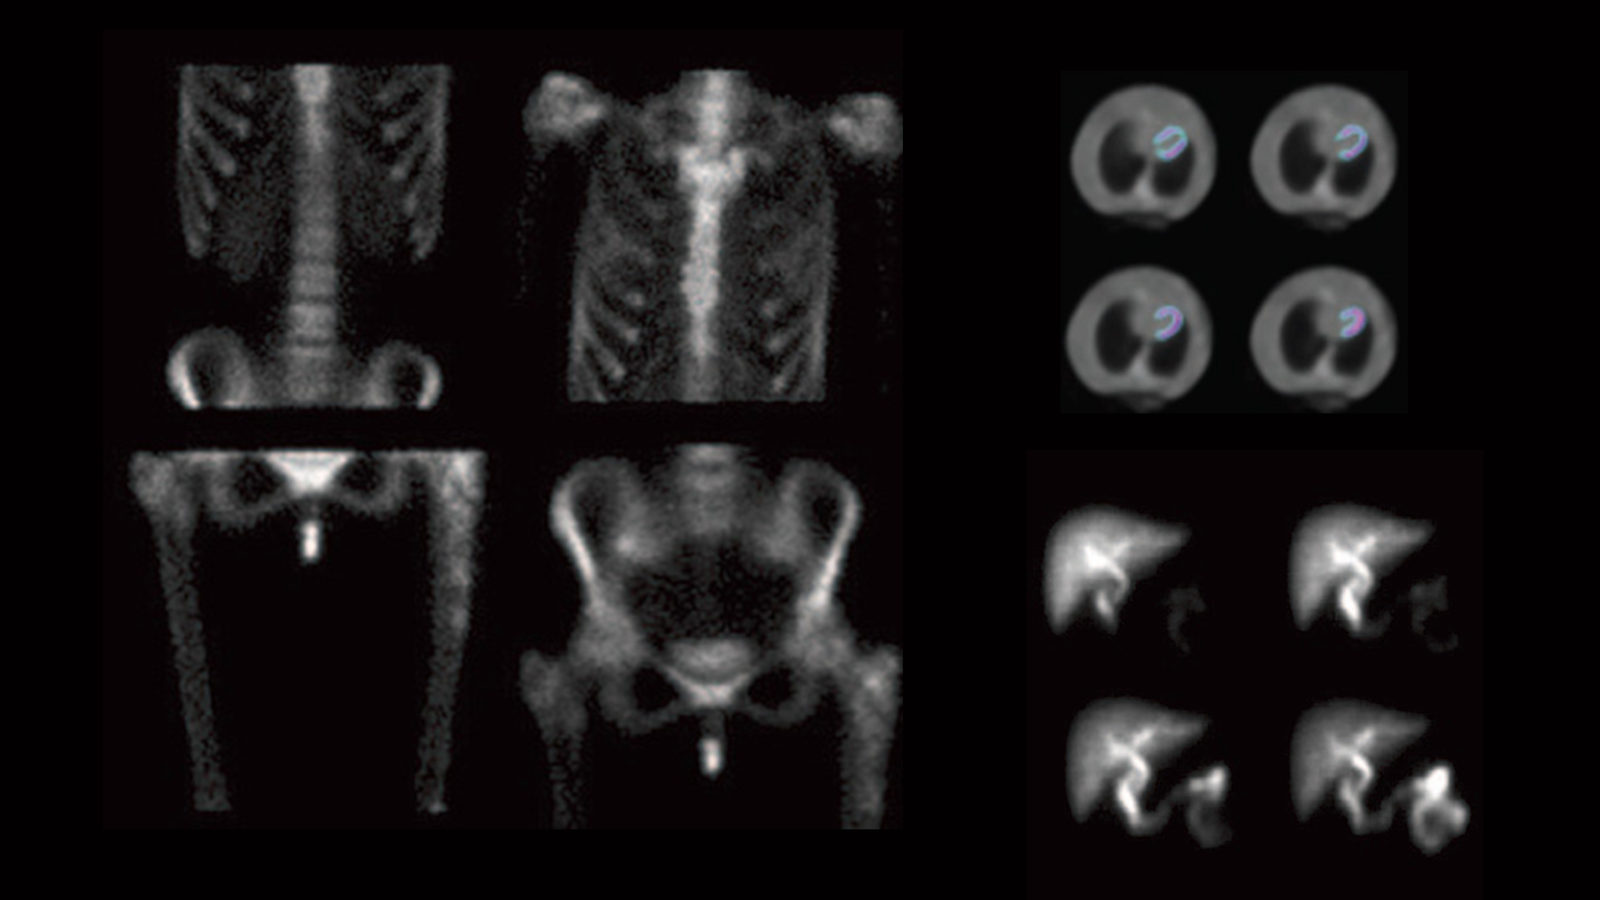

Gamma camera scans of a person suffering from multiple metastastic Gamma Camera Artifacts — four gamma cameras were used to acquire planar images of four‐quadrant bar phantoms and projection. A technologist case study” (5) was. Become familiar with routine performance tests (daily,. Beth israel deaconess medical center department of radiology boston, ma usa. — gamma cameras are complex pieces of equipment which rely on sophisticated hardware and software in. gamma. Gamma Camera Artifacts.